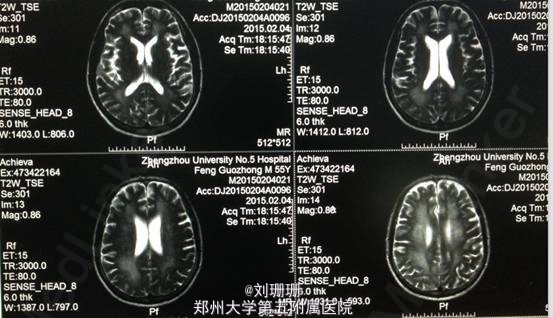

血压 120/80mmHg,神志清,精神一般,面部表情减少,构音清,言语顿挫欠流利,对答反应时间较长,查体欠合作。双侧额纹对称,双眼球各方向活动自如,无眼震,复视及视野缺损,双侧鼻唇沟对称,伸舌基本居中,咽反射灵敏。双上肢肌力Ⅴ级,双下肢肌力Ⅳ级,肌张力偏高无震颤,双侧腱反射对称,双侧巴氏征阴性。痛觉对称,共济运动因智能下降不能配合。双肺呼吸音粗,心率72次/分,律齐,双下肢无水肿。MMSE 18分。 头颅DWI提示双侧侧脑室旁对称性异常信号,结合病史符合一氧化碳中毒脑缺氧缺血所致的脑白质脱髓鞘。